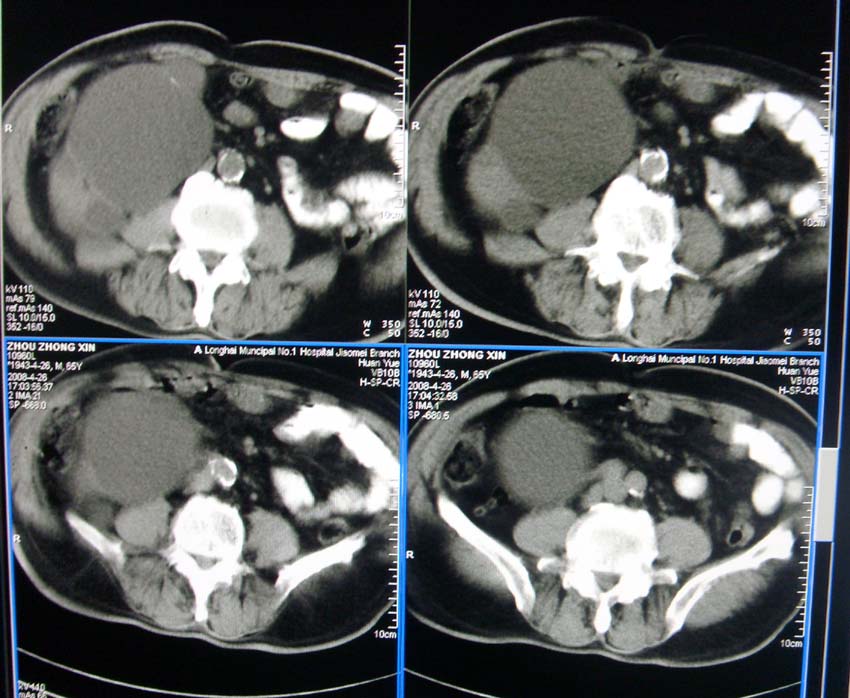

以下是引用liangshusheng在2008-4-27 13:28:00的发言:[br]双肾都有结石,右肾积水波浪状,输尿管积水,建议往下扫

以下是引用zjzjr在2008-4-27 14:25:00的发言:[br]1,右侧多发囊性占位,考虑囊肿可能大。[br]2,肾下部输尿管走行区囊性占位,巨输尿管?建议mru。